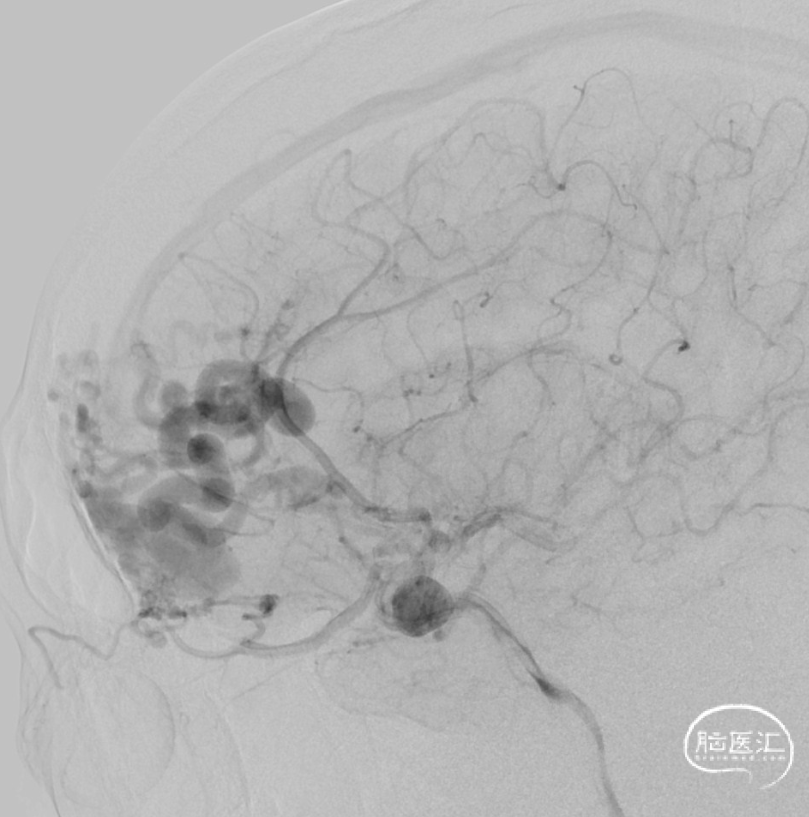

一期治疗

治疗经过